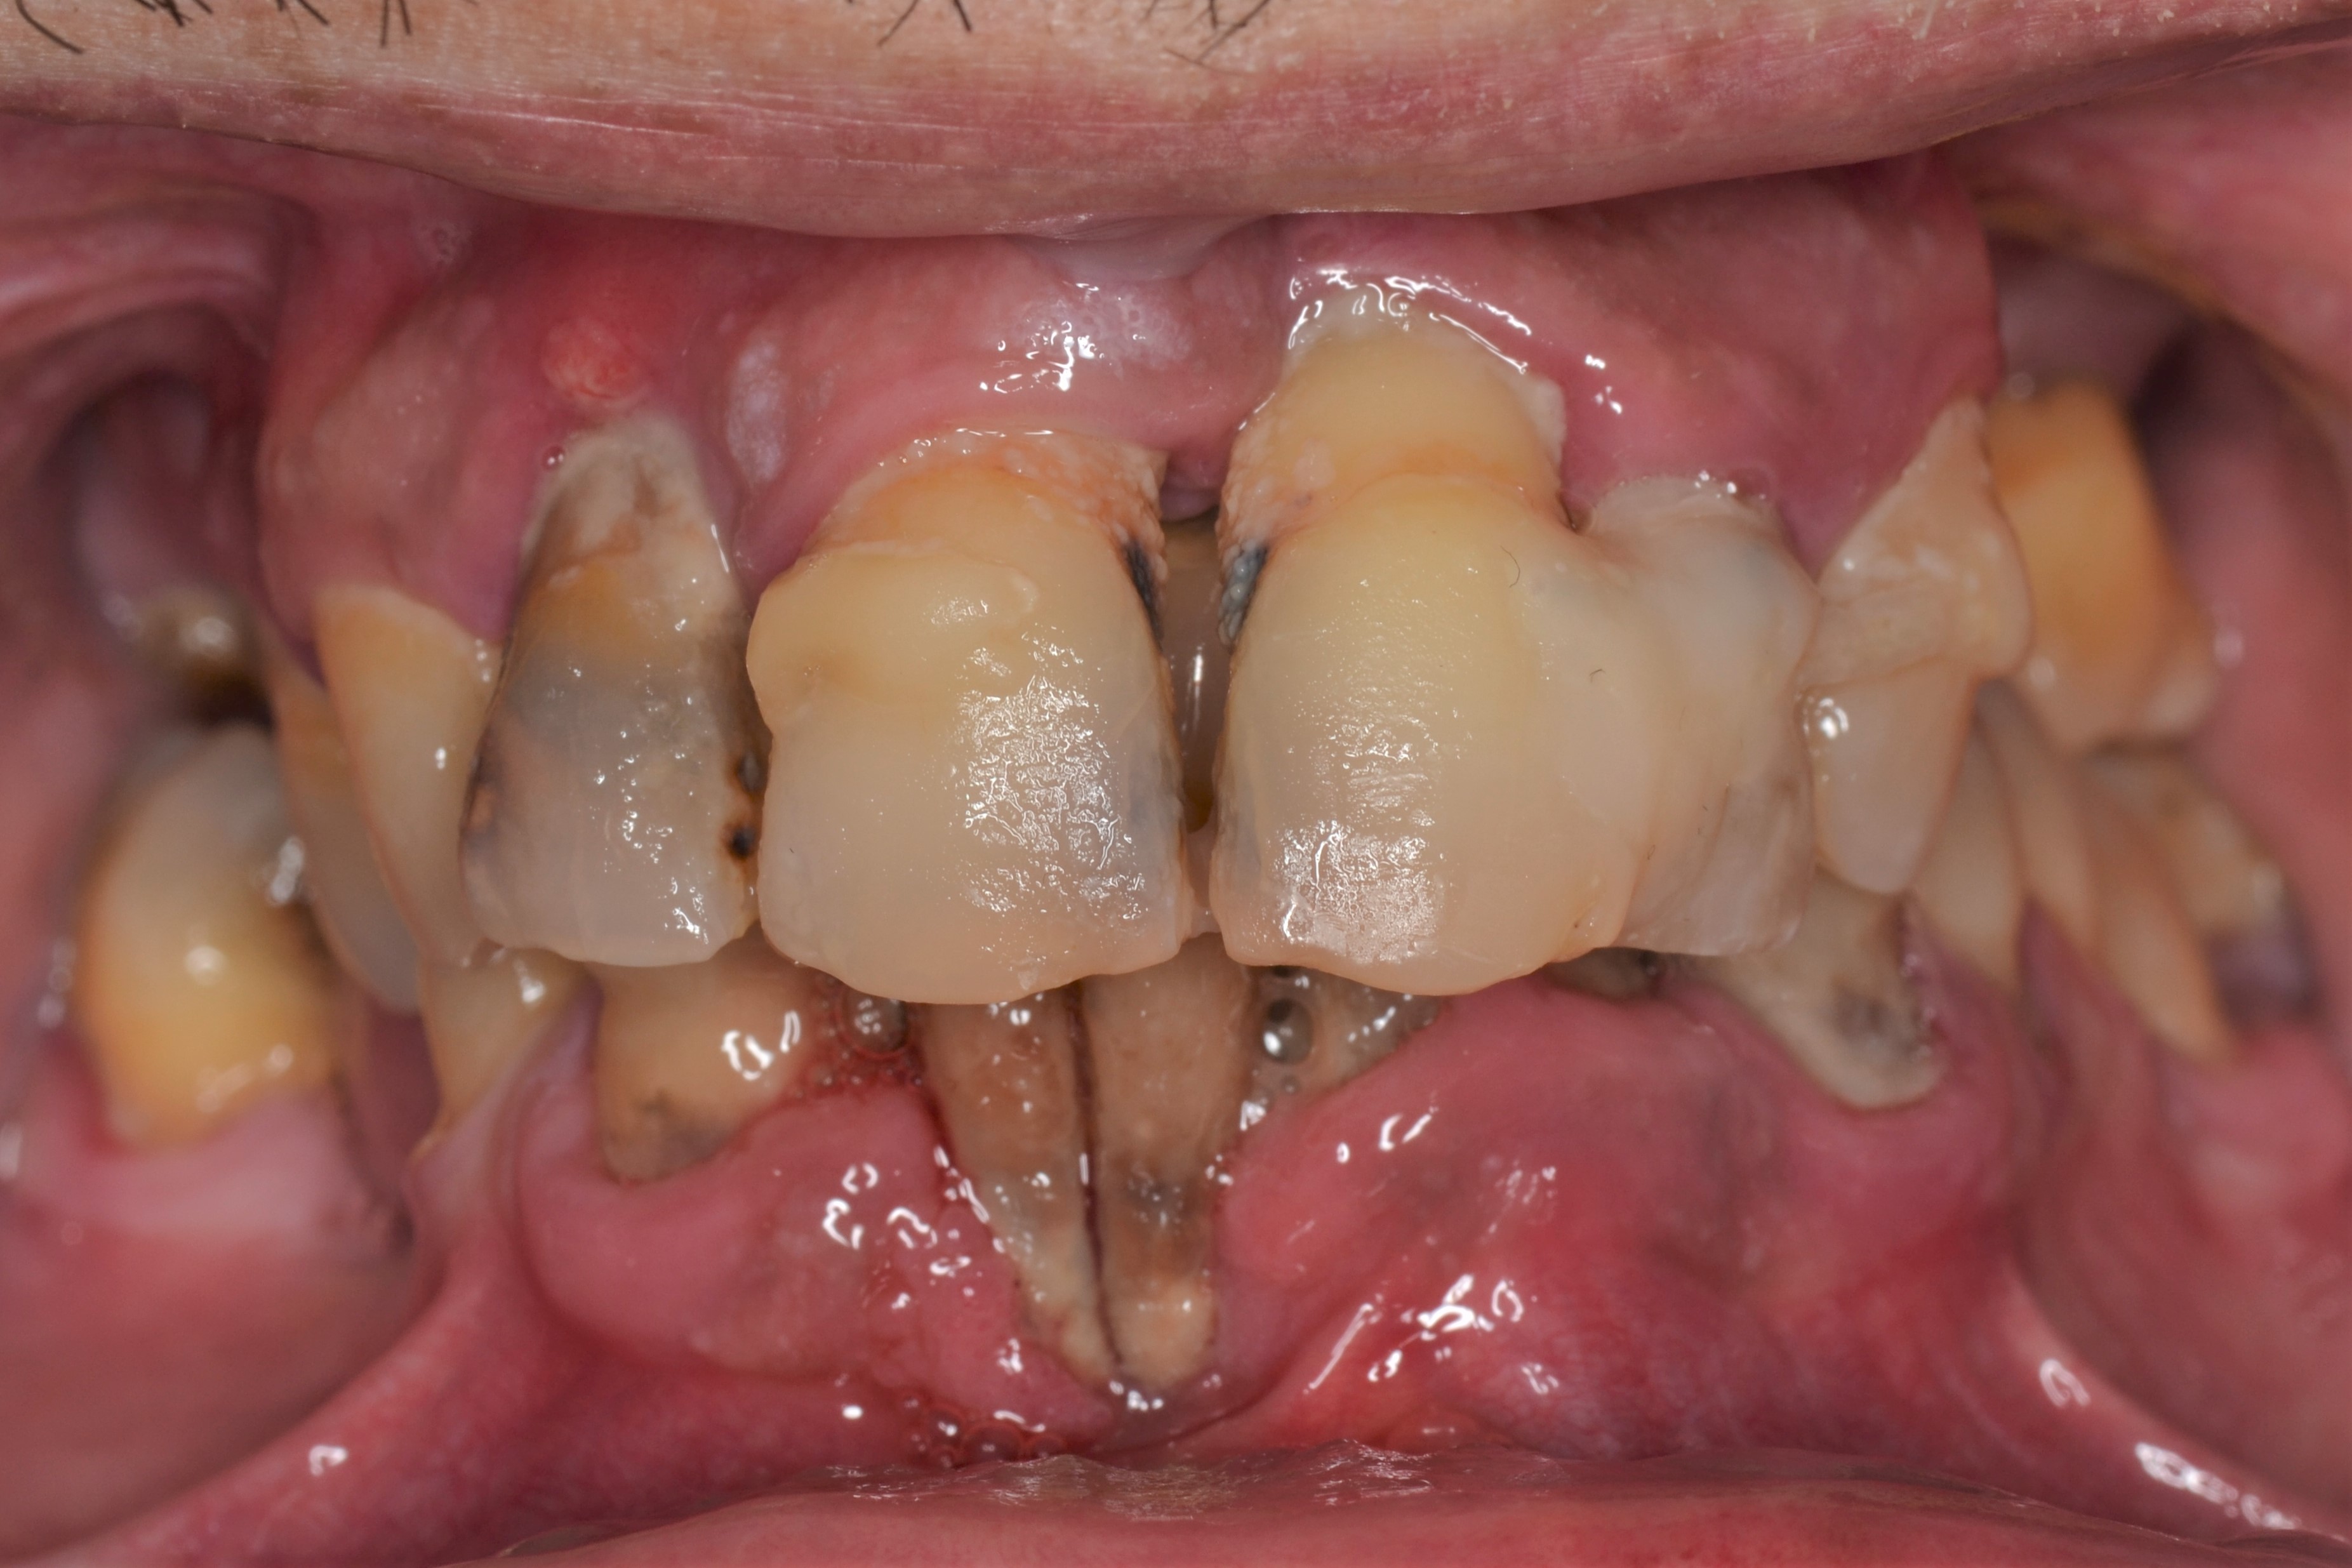

Ο ασθενής αυτός ήταν έντονα δυσαρεστημένος με την εμφάνιση των άνω και κάτω δοντιών του. Τα δοντια του ηταν σε τερματικό στάδιο και η μάσηση ήταν σχεδόν αδύνατη.

Με την χρήση οδοντικών εμφυτευμάτων καταφέραμε να αποκαταστήσουμε το στόμα του.

Οι νέες μεταλλοκεραμικές γέφυρες που κατασκευάστηκαν, αποκατέστησαν την αισθητική ισορροπία του χαμόγελου, την σωστή μάσηση και επανέφεραν την αυτοπεποίθηση του ασθενούς.